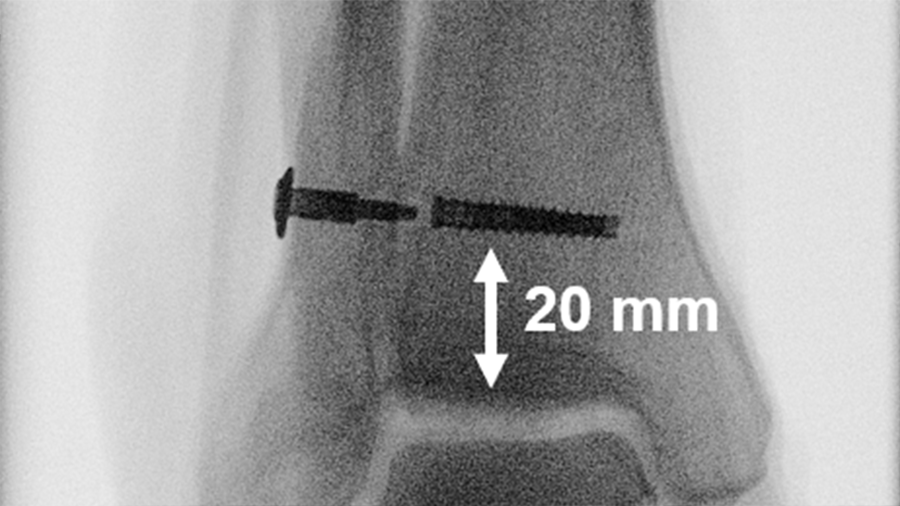

Dynamic screw-suture stabilization system

Evaluating its performance in comparison to a suture-button stabilization of unstable syndesmotic injuries.